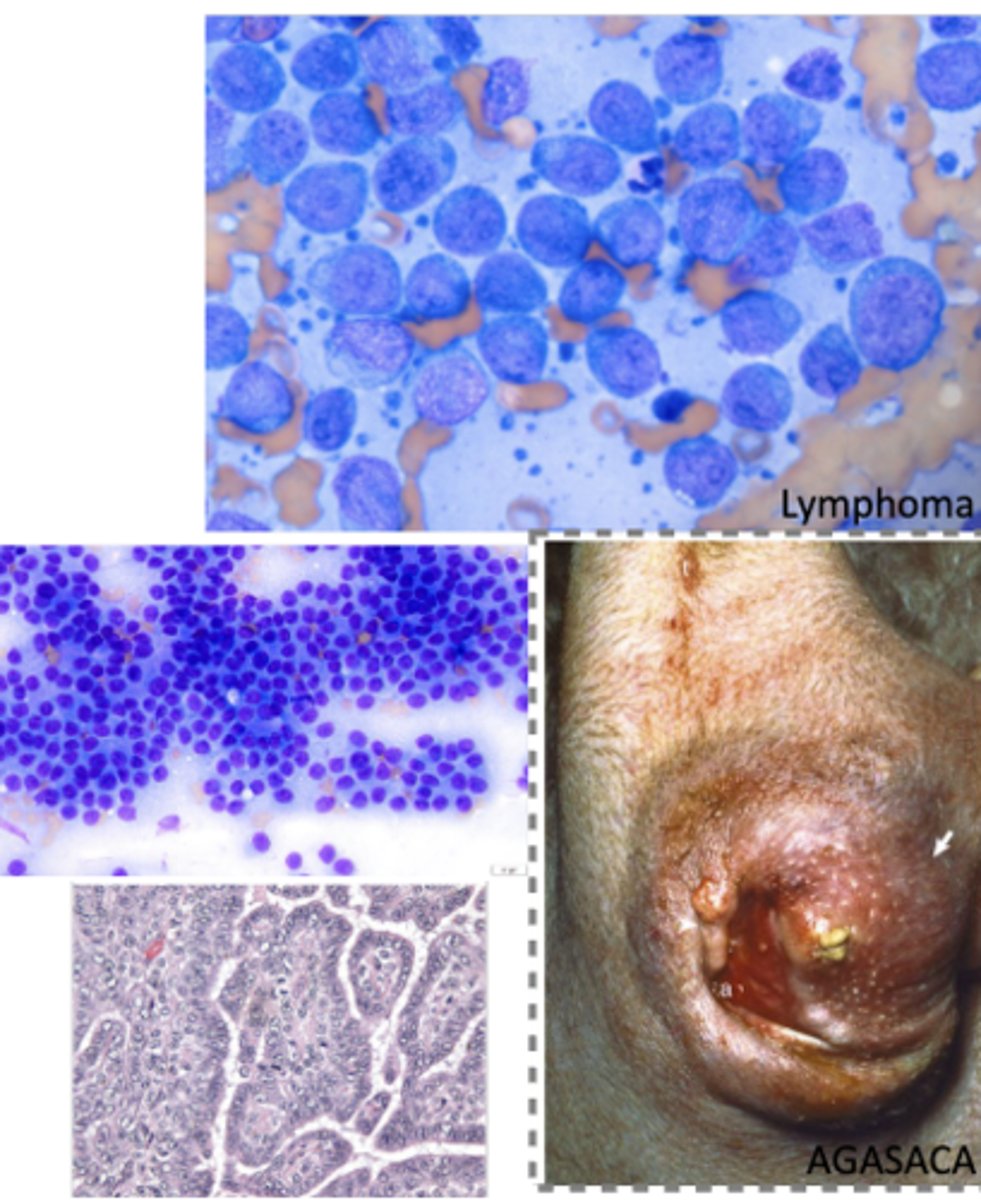

Lymphoma

-lymphocytic tumor originating in the peripheral tissues

What kind of tumor is this?

Mast cell tumor

What kind of round cell tumor is this?

Transmissible Venereal Tumor (TVT)

-TRANSMISSIBLE tumor thru direct contact

What kind of round cell tumor is this?